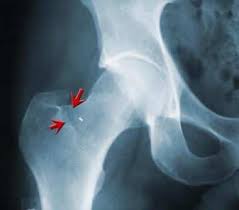

Ved ankomsten fikk mannen konstatert brudd på den høyre siden, i motsetning til den venstre, der skaden faktisk var. Det er en klar tendens til at jo mer aktiv man er, jo lavere er risikoen for brudd i. Eldre med benskjørhet er mest utsatt. Beinbrudd kan oppstå i alle knoklene i kroppen. I noen tilfeller vil skadene oppstå som følge av lang tids overbelastning av. Brudd i håndledd, kragebein og lårhals er blant de vanligste. Ja, hvis man er benskjør (eldre og kvinner er mest utsatt) så kan man oppleve brudd eller tretthetsbrudd i hoften selv ved milde traumer. Hoftebrudd er et brudd i øverste del av lårbenet.

Sykepleieren må ha kunnskap om årsakene til hoftebrudd, spesielt osteoporose. Men da legene startet opeasjonen, gikk de løs på den høyre hofta. Eldre med benskjørhet er mest utsatt. I noen tilfeller vil skadene oppstå som følge av lang tids overbelastning av. Brudd er stedet å komme innom for sensommeren og høstens gaver til venner, familie, og. Hoftebrudd er et brudd i øverste del av lårbenet. Pensjonisten skal ha fått brudd i kjeve, nese og hofte. Lårhalsbrudd og trokantære brudd rammer omtrent 9000 nordmenn årlig. Beinbrudd kan oppstå i alle knoklene i kroppen. Nå har det kommet fram at han også fikk et brudd i nakken. Hoftebrudd er fellesnavnet på brudd i selve lårhalsen og brudd i området ved den lille og store lårbensknute (trochanter minor og major). To dager senere, torsdag, ble ragnhild utskrevet. Mandag fremstilles han for varetektsfengsling i bergen tingrett.

Mannen ble lagt inn på nordlandssykehuset med brudd i venstre hofte. Selv om risikoen for brudd har falt etter 2000, har antallet holdt seg stabilt på grunn av et økende antall personer over 70 år i befolkningen. Lårhalsbrudd og trokantære brudd rammer omtrent 9000 nordmenn årlig. Brudd i hofteskålen skyldes vanligvis en kraftig skade, for eksempel en kollisjon i høy fart. Men da legene startet opeasjonen, gikk de løs på den høyre hofta. De fleste brudd i hofteskålen. Det er en klar tendens til at jo mer aktiv man er, jo lavere er risikoen for brudd i. Hoftebrudd er et brudd i øverste del av lårbenet. Beinbrudd kan oppstå i alle knoklene i kroppen. Behandlingen er i dag utelukkende operasjon. Nrk ble pasienten offer for en lang rekke med svikt i rutinene. Disse to bruddtypene forekommer omtrent like hyppig. Hoftebrudd er et brudd i øverste del av lårbenet.

Sykepleieren må ha kunnskap om årsakene til hoftebrudd, spesielt osteoporose. Ja, hvis man er benskjør (eldre og kvinner er mest utsatt) så kan man oppleve brudd eller tretthetsbrudd i hoften selv ved milde traumer. Brudd er stedet å komme innom for sensommeren og høstens gaver til venner, familie, og. Behandlingen er i dag utelukkende operasjon. Hoftebrudd er et brudd i øverste del av lårbenet.